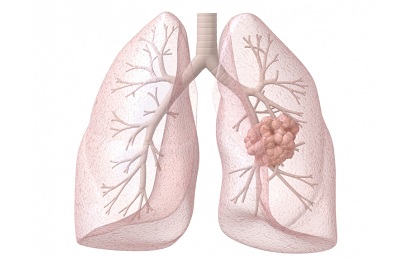

Под раком легких предусматривается злокачественное преобразование и разрастание тканей органа, его мембраны, бронхов и слизистой оболочки. Данный процесс имеет начало на клеточном уровне, под воздействием ряда причин, которые приводят к нарушению регенерации и структуры клеток.

Постепенно развиваясь, в зависимости от некоторых определяющих, злокачественную опухоль легких подразделяют на разновидности.

Они могут развиваться как отдельно, так и в совокупности, представляя наибольшую опасность. В зависимости от того какая опухоль обнаружена, назначается подходящий курс и направление более эффективной терапии.

1-я стадия характеризуется обнаружением опухоли небольшого размера, которая представляет собой единичный очаг без глубокого прорастания в слои органа. Ее размеры устанавливаются до 3 см в диаметре.

- 1а – новообразование достигает размера около 3-х см, начинает прорастать, не переходит на бронхи и лимфоузлы,

- 1b – опухоль не много больше чем 3 см, распространяется на бронхи, но не затрагивает лимфоузлы.

Опухоль при это достигает размеров до 7 см, активно распространяется на бронхи, плевру и альвеолы. Начинается метастазирование региональных лимфатических узлов.